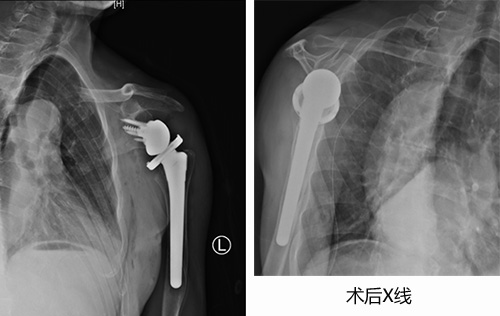

在麻醉手术科医护人员的配合下,创伤中心成功实施了“反置式人工全肩关节置换术”,采用人工假体替代受损的肱骨头和关节盂。术后陈大爷恢复顺利,在科室康复医师的帮助下进行康复锻炼,功能获得明显改善。

反式人工全肩关节置换术是指肩关节假体的球形关节面置于肩胛骨关节盂侧,而盂杯放置于肱骨近端的半限制性人工全肩关节。反肩置换术是肩关节复杂毁损性病变的拯救术式,是利用三角肌来替代肩袖的动能,但由于对适应证限制,手术难度等原因,在国内开展较少。反肩置换主要适用于难以复位固定的老年肱骨近端骨折、陈旧性肱骨近端骨折不愈合或合并骨缺损、骨折内固定失败翻修、难以修复的巨大肩袖撕裂等。作为山东省医师协会骨科分会主委单位、山东省医师协会肩肘外科专业委员会主委单位,创伤中心多年致力于肩肘复杂创伤的研究,该疑难手术的顺利实施,体现了我院处理复杂肩肘创伤病例的领先能力。